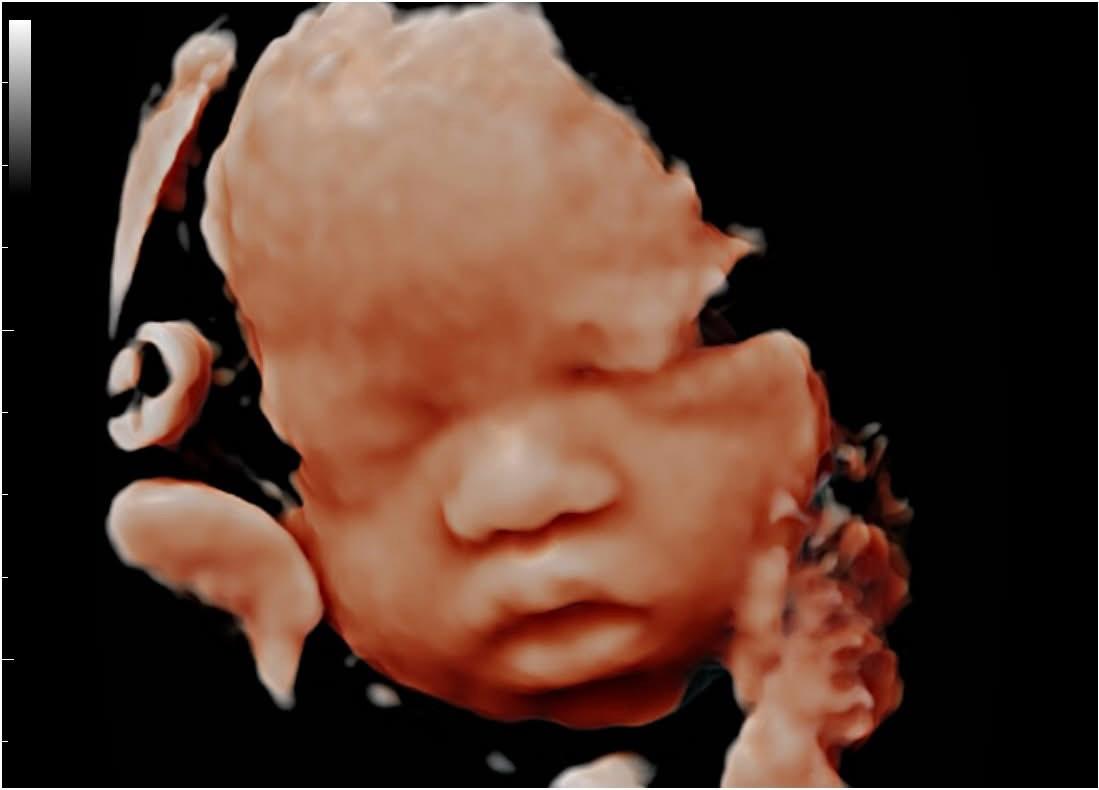

• 5D & 4D and advanced fetal imaging

Can I see my baby’s face clearly in a 4D ultrasound?

Yes, 4D ultrasound can show real-time facial expressions and movements, depending on the baby’s position and amniotic fluid available.